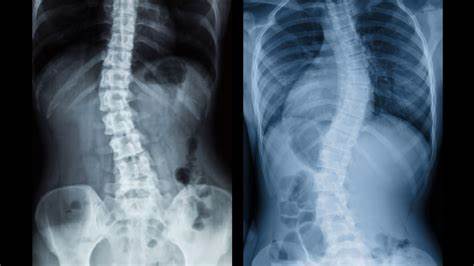

许多人的脊柱并不是完全笔直的,但是医学专家倾向于等到脊柱弯曲超过10度后才诊断脊柱侧弯。脊柱偏离10度是不容易检测到的,它可能只出现在一个肩膀轻微下垂或轻微不均匀的腰围。有些人可以有多达30度的偏差而没有明显的疼痛。

c曲线比s曲线更常见。典型的S形是在脊柱试图自我纠正最初的c形偏差时形成的。

一些报告显示,多达25%的人有脊柱侧弯,但最严重的形式只影响约3%。大多数事件都是特发性的,也就是说原因不明。女孩,特别是青春期前的女孩,比男孩更容易发生脊柱侧弯。这可能与女孩早期的生长高峰有关,通常在10到14岁之间。成人脊柱侧凸的发病是罕见的。神经肌肉疾病,如多发性硬化症或极差的姿势会导致脊椎明显弯曲。